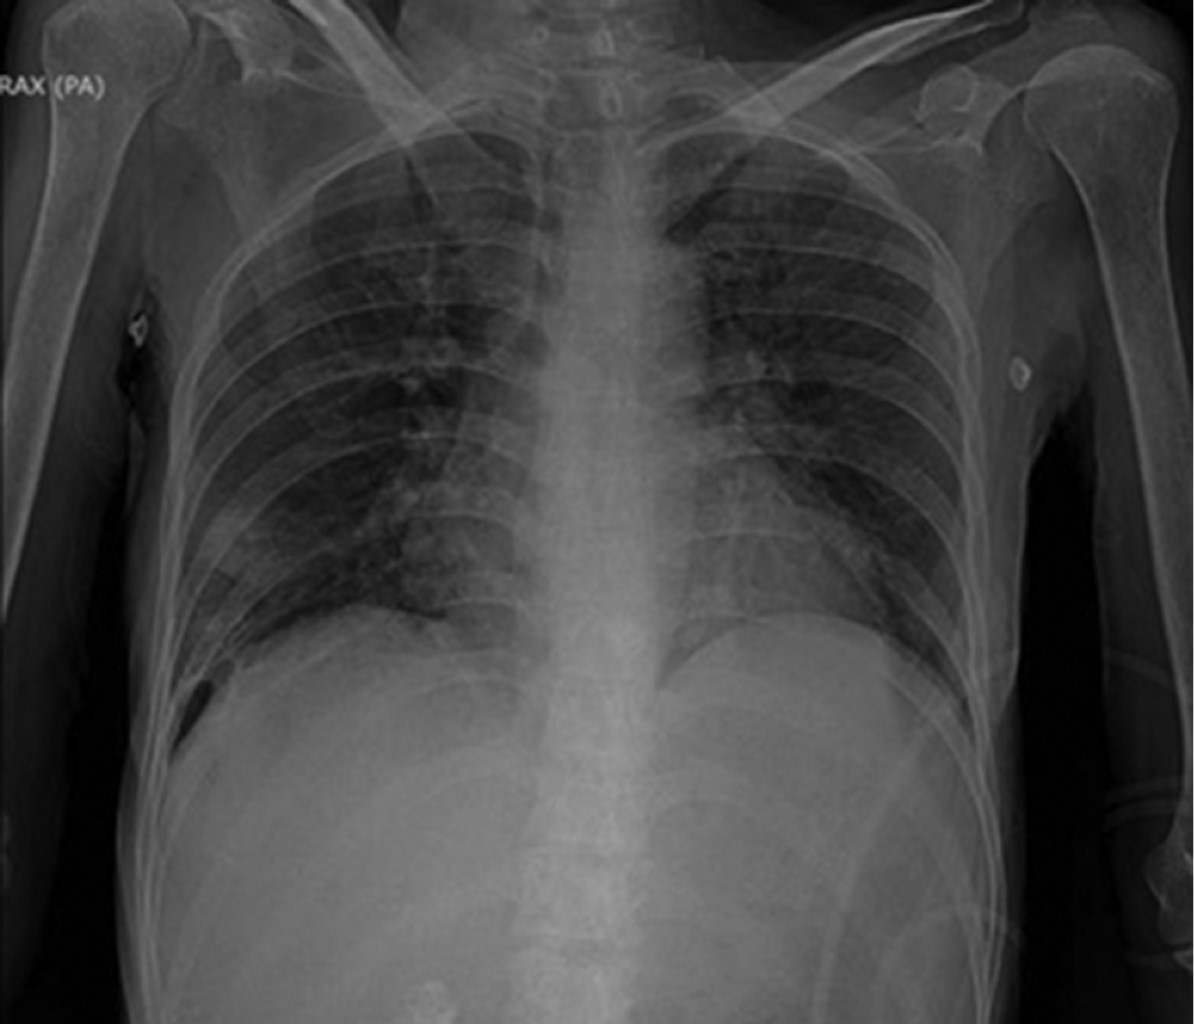

Mujer de 40 años de edad postnefrectomía secundario a absceso perirrenal, deterioro hemodinámico y respiratorio que requirió manejo en la Unidad de Cuidados Intensivos (UCI). La paciente presentó ventilación prolongada con necesidad de traqueotomía. Después de 38 días de estancia en la UCI se logra la decanulación de traqueostomía con éxito. Sin embargo, al cuarto día posterior a la decanulación presenta atelectasia completa del pulmón izquierdo sin datos de inestabilidad respiratoria (Figura 1). Las atelectasias completas se caracterizan radiológicamente por pérdida de la aireación pulmonar, radiopacidad de la región afectada, pérdida de la silueta cardiaca, ascenso de la cúpula diafragmática, desplazamiento de las estructuras mediastinales y tráquea de forma ipsilateral. Debido a las características del caso y las posibles complicaciones de manejo por medio de broncoscopia, se decide abordar de forma conservadora por medio de técnicas de fisioterapia pulmonar. Dentro del manejo fisioterapéutico se utilizaron técnicas de expansión torácica con apoyo de presión positiva con bolsa válvula mascarilla + válvula de presión positiva al final de la espiración (PEEP) de 10 cmH2O, tos asistida manual, fisioterapia de tórax para el manejo de secreciones y decúbito inspiratorio controlado (EDIC). Esta última técnica prioriza la ventilación hemipulmonar colocando en supralateral el pulmón a ventilar seguido de inspiraciones guiadas y finalizadas con espiraciones asistidas por compresión manual del tórax. Después de la radiografía de control a las seis horas (Figura 2) se decide la utilización de ventilación mecánica no invasiva durante la noche como manejo coadyuvante con una presión soporte 5 cmH2O y una PEEP de 5 cmH2O. Se logra el egreso hospitalario a los ocho días del evento con seguimiento médico y fisioterapéutico (Figura 3).

Figura 3